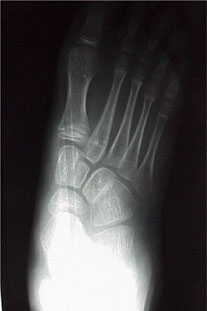

Physicians may evaluate the transverse plane component by noting the medial bulge produced by the uncovered talar head and the percentage of talar head coverage on an AP weightbearing radiograph.

Transverse plane deformity. These children stand with the calcaneus in 10 degrees of heel eversion. Subtalar range of motion averages 30 degrees of inversion and 10 degrees of eversion. When one views this from above, there is a major prominence of the talar head medially. This is confirmed on AP weightbearing radiographs. The medial half of the talar head is not covered because the navicular is placed dorsally and laterally. Supinating the rearfoot will cover the talar head but this results in an unacceptable varus position of the calcaneus.

Radiographs show a very wide AP talocalcaneal angle with an abducted forefoot. The lateral view shows sagittal instability of the medial column. The deformity is most pronounced on the transverse plane.